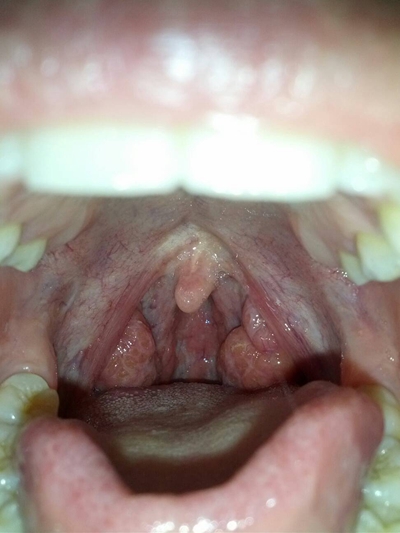

食道炎的症狀圖 (7)